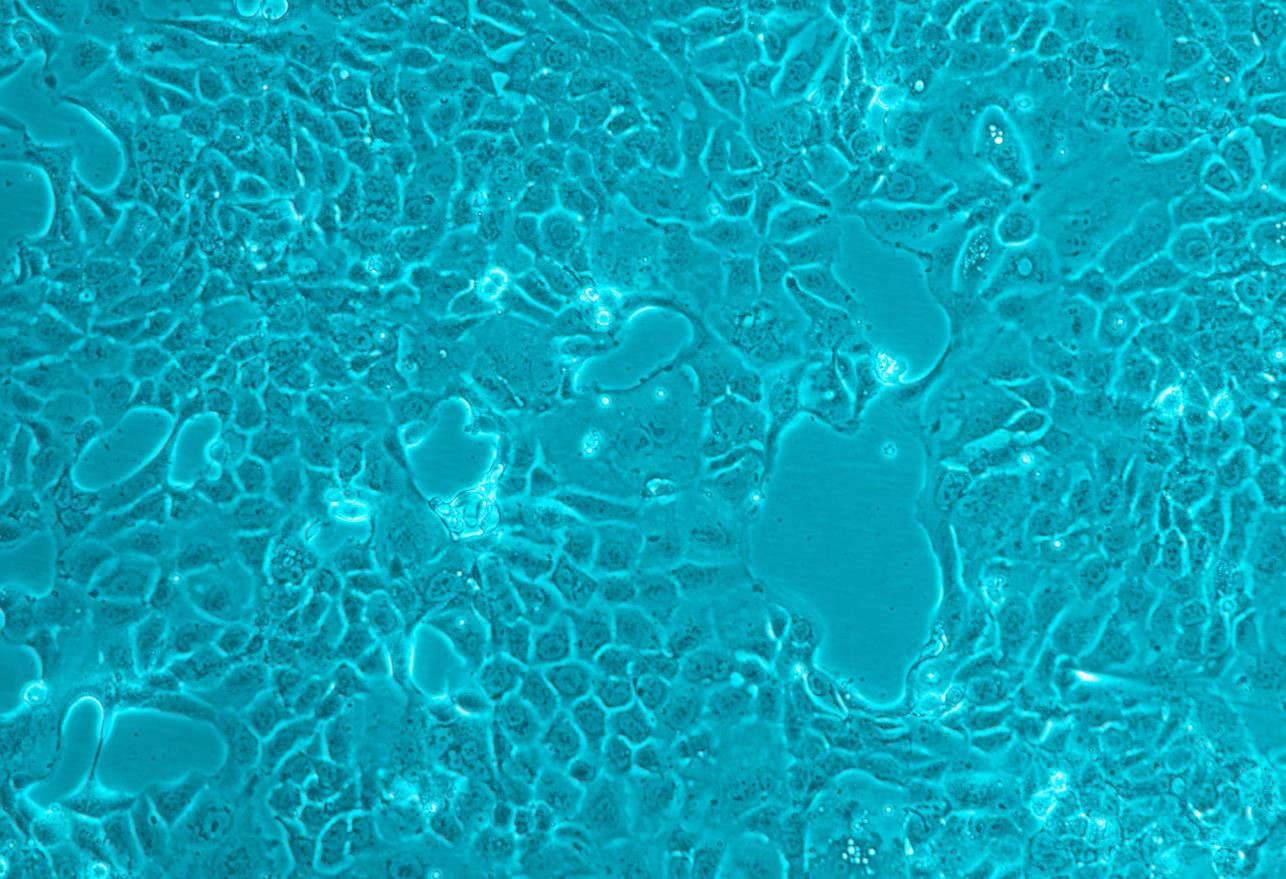

形态 |

上皮细胞样 |

生长特征 |

贴壁生长 |